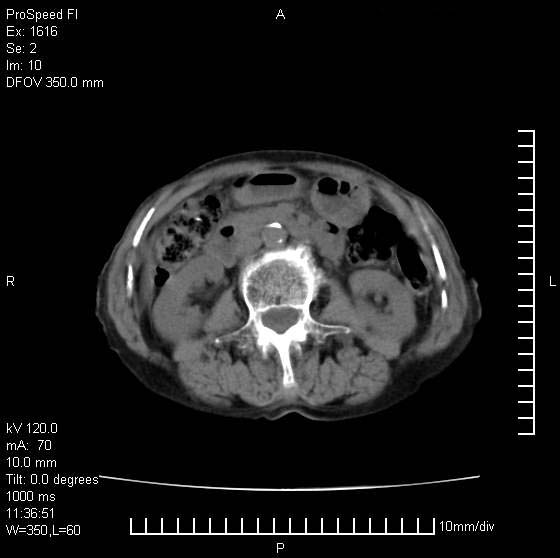

患者无明显临床症状,肝左叶发现一个圆形密度不均的低密度灶,边界较清楚,大小37x45mm,ct值35-70,患者犹豫做增强,如有增强片,我再发上,现先请各位老师会诊.

左肝外叶可见较大圆形低密度影,病灶可见较光整清晰边界,病灶内可见多量条状稍高密度影,右肝前叶亦可见圆形结节状低密度影,边界清晰,密度均匀,考虑1肝多发囊肿,左肝囊肿内出血2肝包虫病3左巨块型肝癌出血合并右肝转移或合并右肝囊肿

肝左叶类圆形低密度影,内可见略高密度影,边界清晰周边可见环形低密度带,考虑肝腺瘤可能,建议增强扫描除外肝血管瘤与肝癌

肝左叶类圆形低密度影,内可见略高密度影,边界清晰周边可见环形低密度带,考虑肝血管瘤

肝左叶不均匀占位,内有斑片状高密度出血灶,内侧缘似有假包膜,腹主动脉周围及肝门区结构紊乱,似有增大淋巴结,考虑:肝左叶hcc并淋巴结转移。建议增强扫描除外其他。